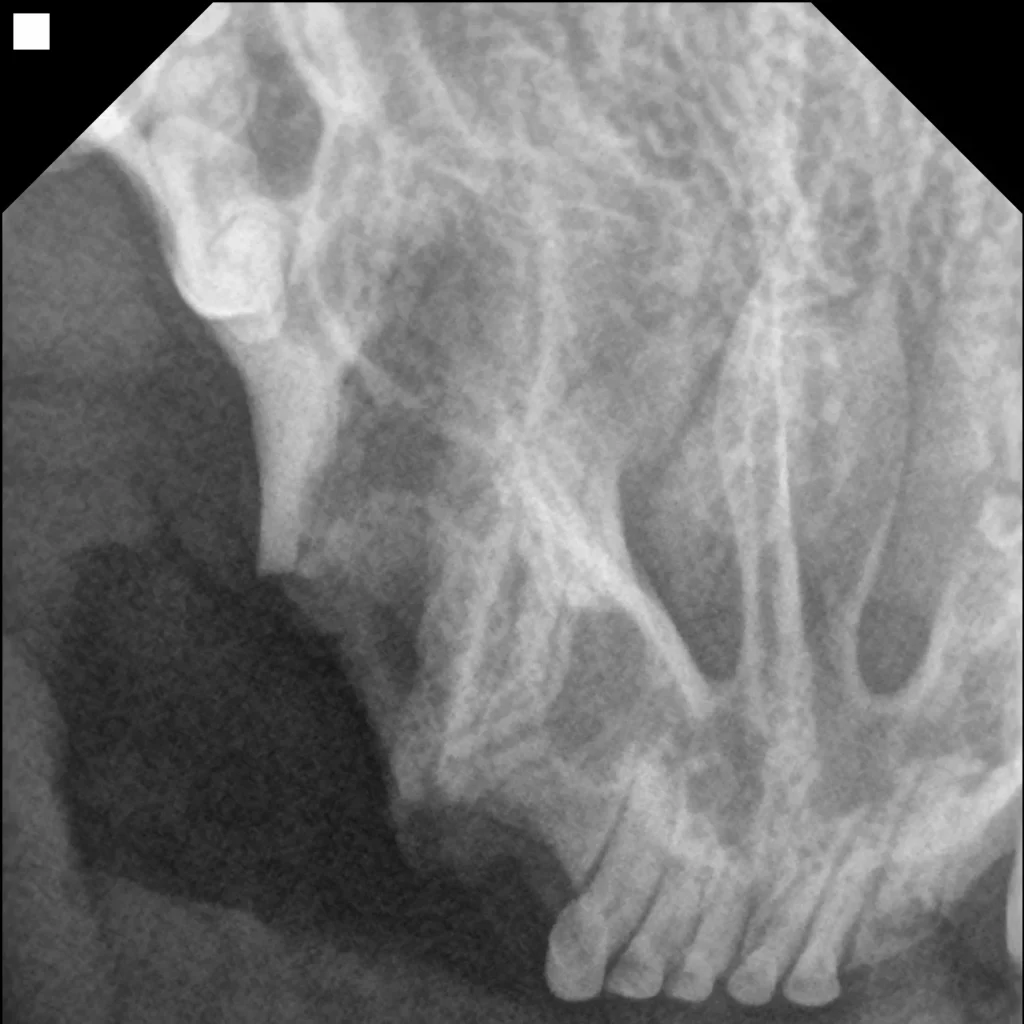

• 만성 구내염(feline chronic gingivostomatitis, FCGS)으로 목구멍염까지 확인되는 경우 통증 완화를 위해 전발치를 진행합니다.

• 뿌리를 남기지 않았는지 수술 전/후 치과방사선 촬영을 통해 확인합니다.

발치 후 치과 방사선​